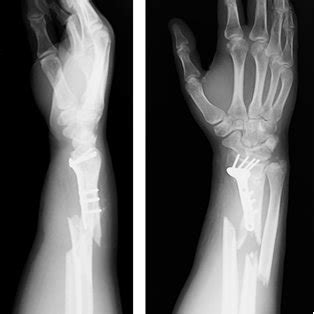

The stability of the implant dictates the type of. The study of peri implant fractures has been mentioned in research publications which can be found using our bioinformatics tool below. Epidemiology, morbility, mortality, treatment and functional outcome analysis.

Epidemiology, morbility, mortality, treatment and functional outcome analysis. Collinge}, journal={journal of orthopaedic trauma}, year={2017}, volume={31 5}, pages={. Antegrade intramedullary nailing of the femur is an effective. He was discharged from follow up after complete healing of the fracture. L'implant dentaire est une pièce ancrée dans l'os de la mâchoire qui sert de racine dentaire artificielle. The red arrow indicated the fracture. Epidemiology, morbility, mortality, treatment and functional outcome analysis. • follow standard principles of fixation • must achieve stable anatomic fixation. A prospective multi center observational collaborative study. Implant fractures occurring distal to an antegrade femoral. Ú critical role for radiologist to recognize intended surgical location prior to surgery. The soft tissues become inflamed whereas the alveolar bone (hard tissue). Management is challenging because of alterations in anatomy, the presence of orthopaedic implants and phenomena such as stress shielding, disuse osteopenia and fracture remodeling. Dental implants are made of commercially pure titanium or titanium alloy and are generally quite strong. Principles of operative fixation and future directions.}, author={frank a. Epidemiology of periprosthetic fracture of the femur in 32 644 primary total hip arthroplasties: La perte d'une dent peut être causée par de nombreux en général, la pose d'implants dentaires ne nécessite pas d'hospitalisation.